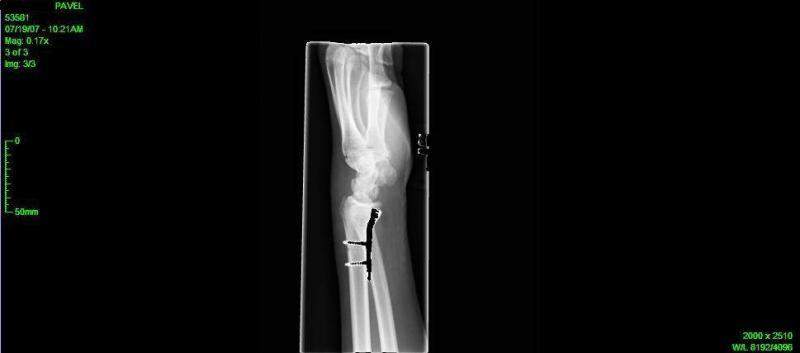

Недавно руку поломал, и чтобы кости вместе скрепить вставили титановую фиговину.

Подвижность кисти уже не такая, но думаю это временно. В классическую позицию трудно ставить.

А пальцы нормально двигаются :)